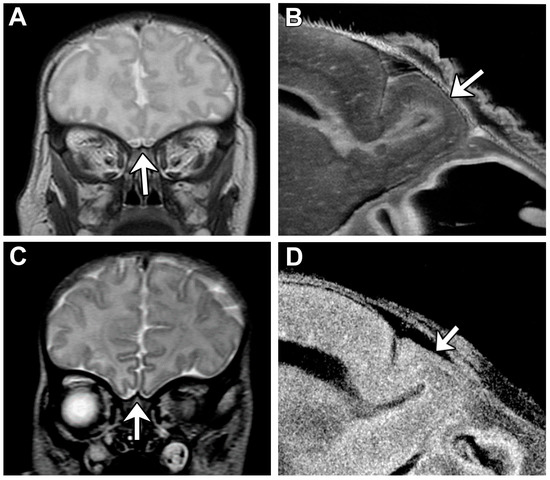

Lack of oral feeding before neonatal hospital discharge was associated with multiple morphological abnormalities of the components of the BDS including cerebellar hemispheres and vermis, hippocampus, bilateral olfactory bulbs and olfactory sulci, corpus callosum, increased supratentorial extra-axial fluid, as well as total increased BDS (Table 7). Hospital length of stay was associated with dysplasia of the cerebellar hemispheres and vermis, hippocampus, choroid plexus, brainstem, increased supratentorial axial fluid, and BDS (Table 7). A diagnosis of dysphasia was associated with dysplasia of the brain stem ((p = 0.001) Table 7). Gastrointestinal dysmotility, aspiration, gastroesophageal reflux, malrotation, and vocal cord paralysis demonstrated no significant associations with brain dysplasia (Table 7). Figure 2 panels A–D show some of the variations in hippocampal anatomy seen in the human population compared against that seen in the mouse in panels E and F. Figure 3 demonstrates olfactory bulb abnormalities in human infant CHD vs. control (A/C) and the mouse model (B/D). Figure 4 demonstrates cerebellar abnormalities in the human infant CHD vs. controls (A,B) and the mouse model (E,F).